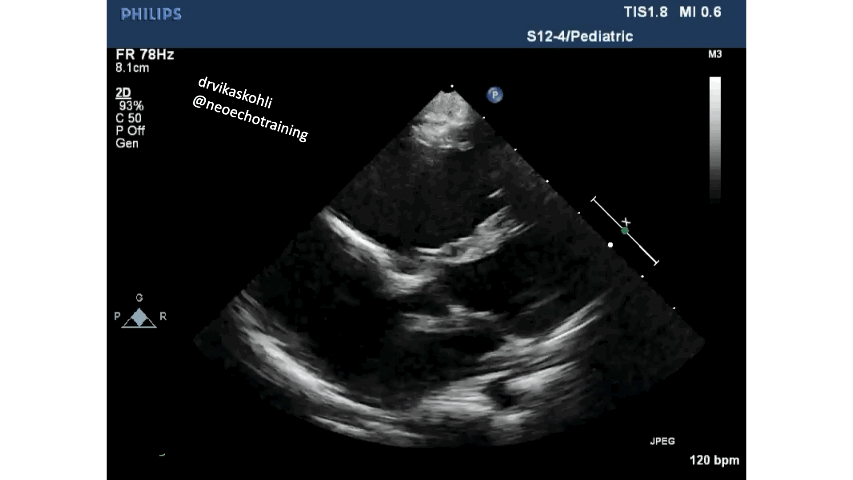

The diagnostic abnormality includes:

Displacement of Septal leaflet of tricuspid valve apically.

c). The Septal leaflet if you look carefully ( and in the picture below) is stuck to the septum and moves only near the apex of the RV:

The RV from the true tricuspid attachment to the new septal leaflet attachment is referred to as Atrialized RV.